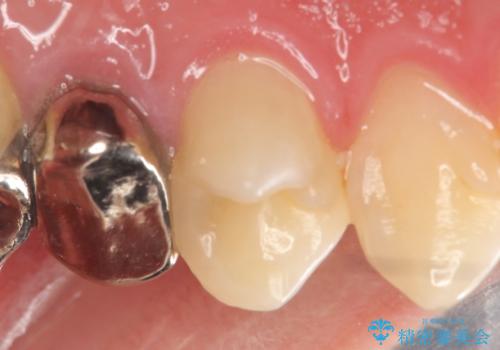

そのため左上4番目の歯は根管治療を行い、歯茎の膿の出口の消失を確認後、オールセラミッククラウンによる補綴を行いました。

今回用いたオールセラミッククラウンはジルコニアフレームという白い素材の上にセラミックを盛っているため、審美性が非常に高いのが特徴です。

また、ジルコニアは人工ダイヤモンドの材料にも使われているほど高い強度を持っており、そのためオールセラミッククラウンは審美性だけでなく、奥歯やブリッジの補綴も可能とするクラウンです。